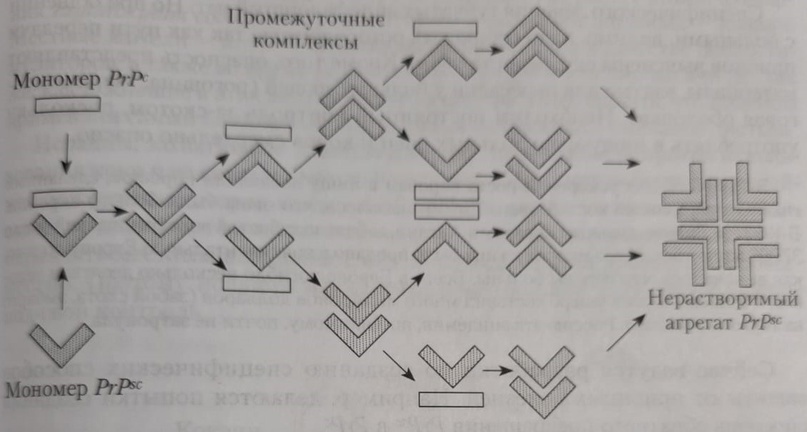

Позже появились другие теории. Так, согласно одной из них, причина инфекционности PrPSc в следующем: инфекционный прион является зародышем для цепочечной полимеризации нормальных прионов. Конверсия PrPС в PrPSc представляет собой посттрансляционный процесс, включающий глубокое конформационное изменение, являющееся фундаментальным событием, лежащим в основе размножения инфекционных прионов. Эта форма обнаружена в организме людей и животных, больных прионными заболеваниями – трансмиссивными спонгиоформными (губкообразными) энцефалопатиями. В 1997 году за это открытие С. Прузинеру была вручена Нобелевская премия. Таким образом, установлено, что инфекционным агентом болезни Кройтцфельдта-Якоба, куру и скрепи служит белок.

Патогенез поражения обусловлен мутацией гена, кодирующего PrPС, программирующего выработку другой, мутированной, плоской формы – PrPSc с изменёнными аминокислотами. В другом случае конверсия PrPС в PrPSc представляет собой посттрансляционный процесс, включающий глубокое конформационное изменение, являющееся фундаментальным событием, лежащим в основе размножения инфекционных прионов. Молекула PrPSc соединяется с молекулой PrPС с образованием димерного продукта, трансформирующегося с двумя молекулами PrPSc. В следующем цикле две молекулы PrPС соединяются с двумя молекулами PrPSc, что обеспечивает экспоненциальное образование молекул PrPSc. Белок PrPС – короткоживущий (период полураспада 5 – 6 часов), растворимый в жидких средах организма.

В противоположность этому инфекционный белок PrPSc накапливается в цитоплазменных везикулах, что приводит к последующему нарушению функции синапсов и развитию глубоких неврологических дефектов. Позднее PrPSc высвобождается во внеклеточное пространство и откладывается в виде амилоидных бляшек. PrPSc форма обнаружена в организме людей и животных, больных прионными заболеваниями – трансмиссивными спонгиоформными (губкообразными) энцефалопатиями.